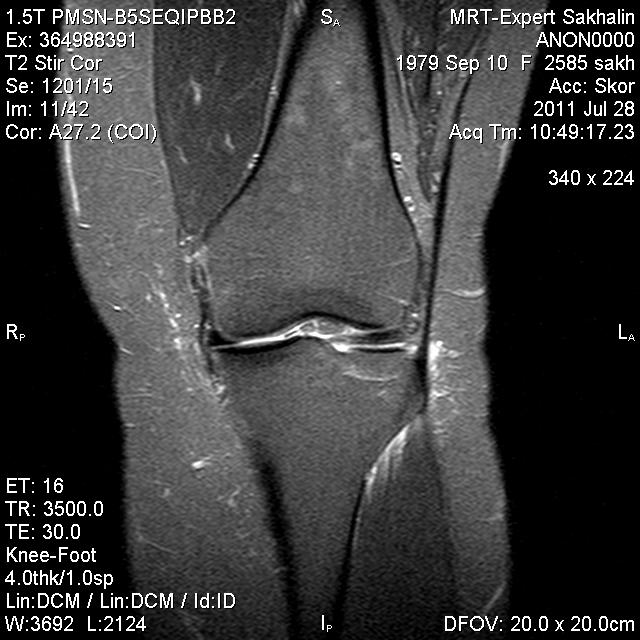

Коленный сустав

Подглядела случай у коллеги.

Что это может быть?

P.S. В костях - это, скорее всего, резидуальный красный костный мозг.

участки гемопоэтического костного мозга